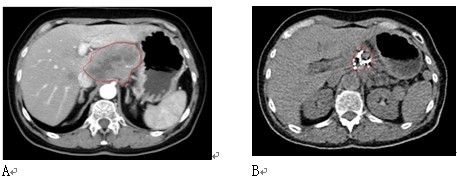

(1)2008年,我们报告49例冷冻加上125碘粒子植入治疗49例局部进展性胰腺癌的结果【14】。49例中,13例接受手术中冷冻,36例接受经皮冷冻。在接受经皮冷冻的患者中,17例接受了第2次冷冻,3例共接受3次冷冻。碘粒子于35例在冷冻的同时植入,14例在冷冻后3-9天植入。术后3个月内作CT评价肿瘤反应,结果显示完全反应(CR)、部分反应(PR)、稳定(SD)和进展(PD)分别为20.4%、38.8%、30.6%和10.2%(图1-5)。中位随访期18个月(5-40月)。中位生存期16.2月。26例(53.1%)生存12个月或更长,其中1例生存54个月,最后死于原发性肺癌。至死胰腺肿瘤未复发(见图1)。36例在随访期死亡,其中17例死于癌播散,11例死于肝转移伴肝衰竭,5例死于心脑疾病。1、2和3年生存率分别为63.1%、22.8%和9.5%。

图1 男性,80岁。胰腺沟突部腺癌。A:治疗前,B:冷冻加碘粒子植入后3个月复查,C:治疗后12个月复查。

患者活存54个月,死于二重癌肺癌。

图2 男性,61岁。胰腺体尾部腺癌伴肝转移。A:治疗前;B:冷冻-碘粒子联合治疗后1个月复查;

C::治疗后6个月复查。血液CA19-9降至40IU以下。患者生存27个月。